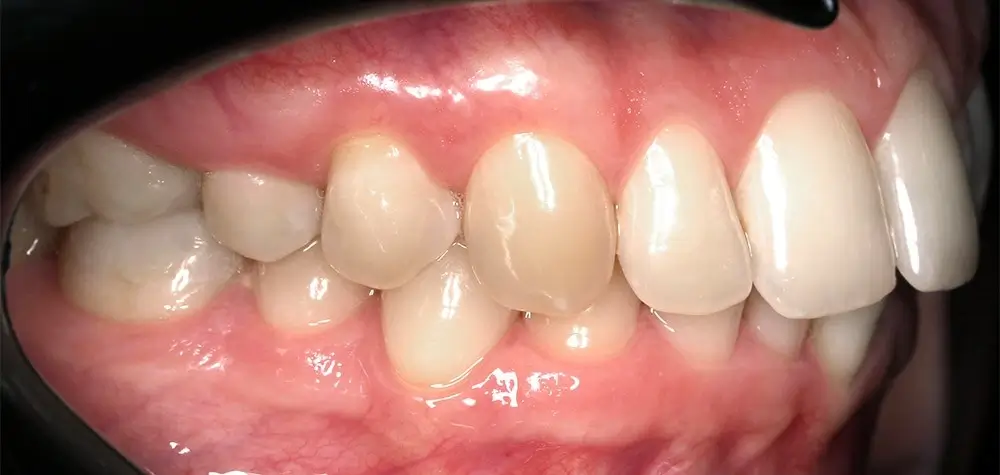

Кейс 13

Булгач (Мочалова) Галина Игоревна

Количество кап ВЧ 19

Количество кап НЧ 24

ДО

ПОСЛЕ